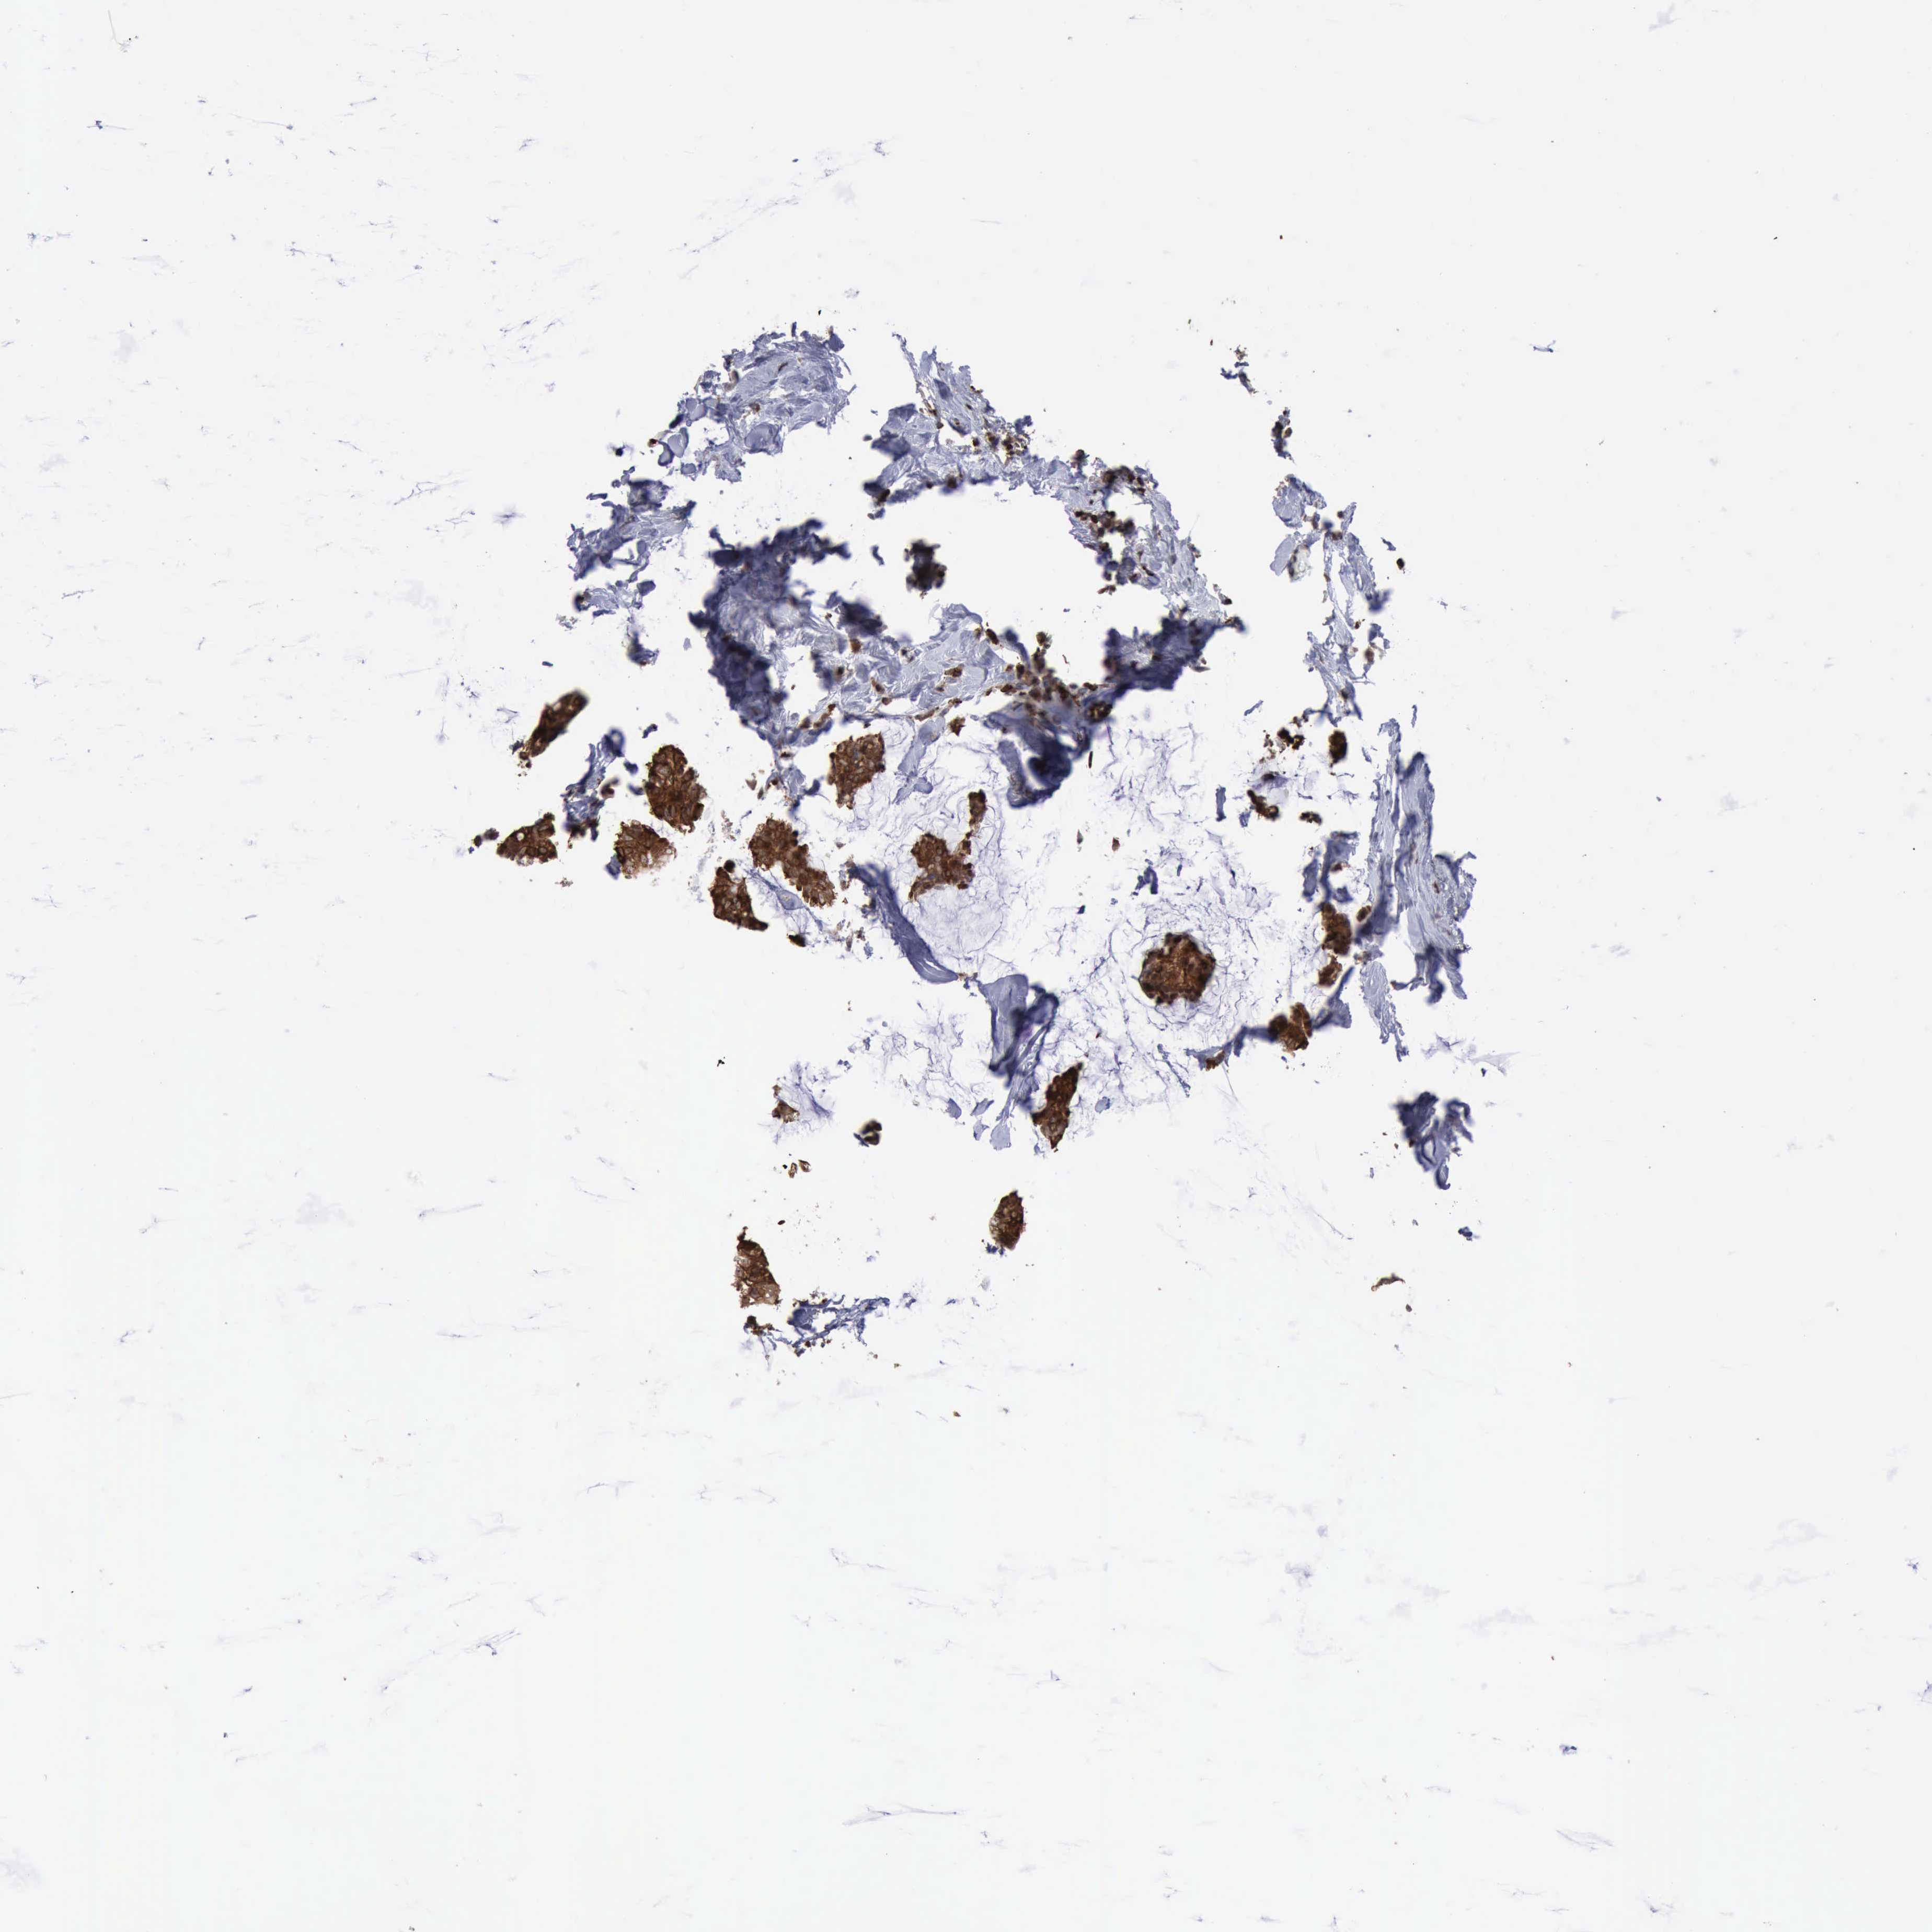

CANCER BREAST CANCER Show tissue menu

BRCA TCGA BRCA VALIDATION PROTEIN EXPRESSION

ANTIBODIES

AND

VALIDATION